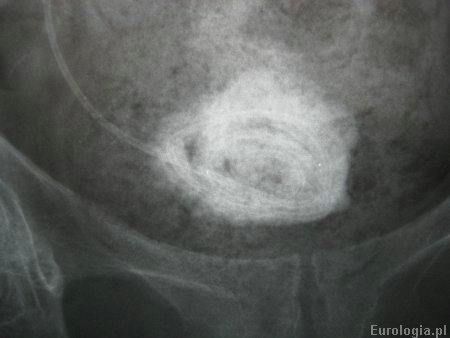

Fot. Zdjęcie końca pećherzowego cewnika DJ w powiększeniu.

Fot. Kalcyfikacja cewnika DJ - złóg średnicy 5 cm na końcu pęcherzowym cewnika.